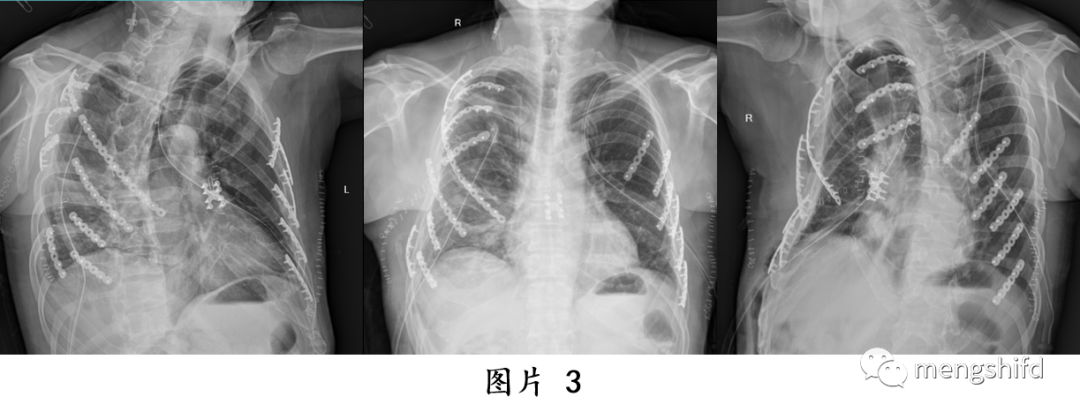

多发肋骨骨折和胸骨骨折合并连枷胸的手术治疗方